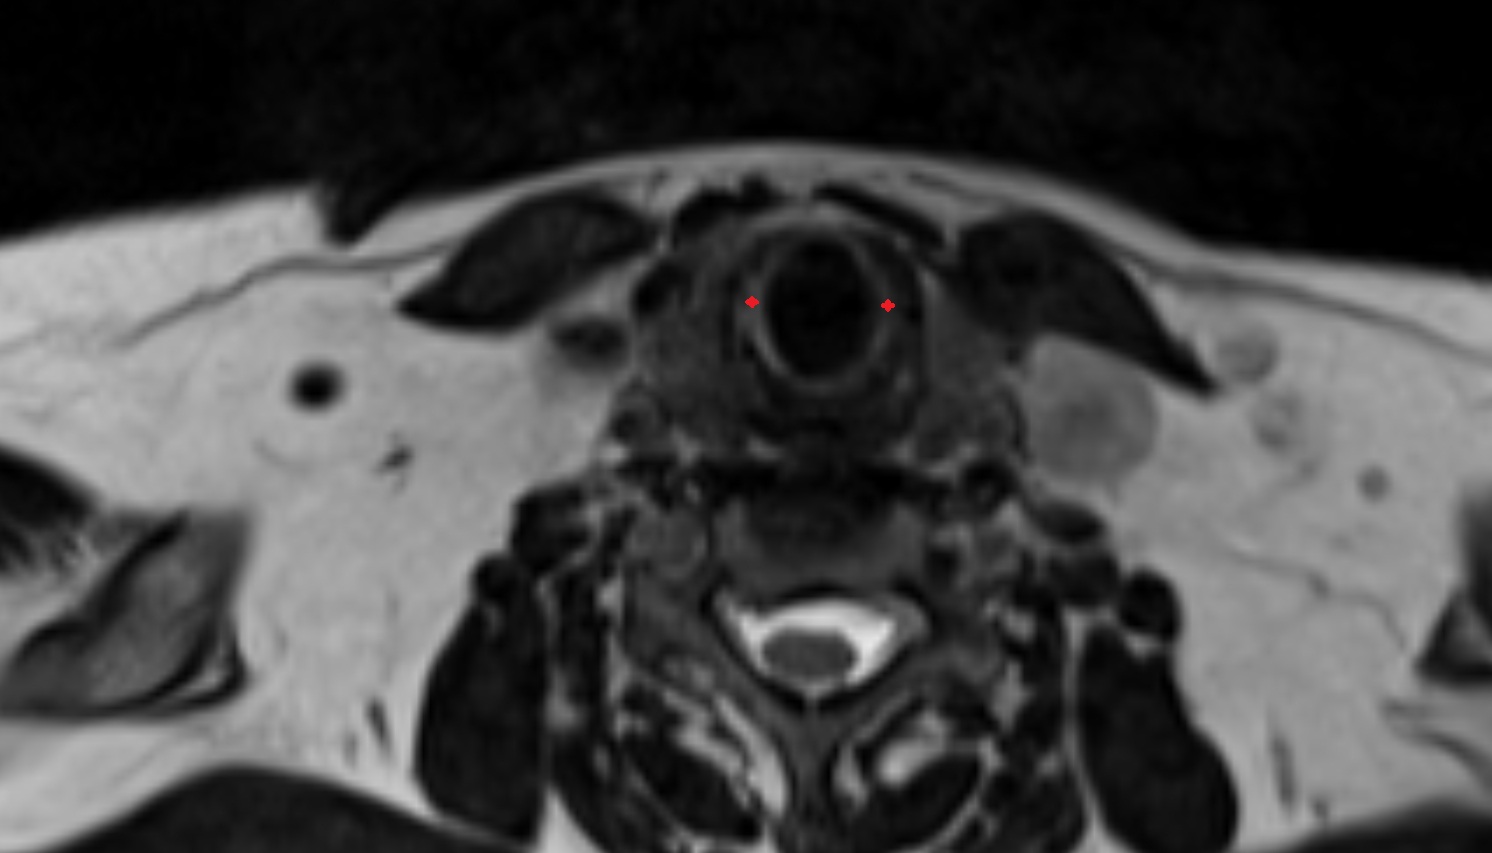

- Peripheral zone of prostate

- Anterior Fibromuscular Stroma of prostate

- Central zone of prostate

- Transitional zone of prostate